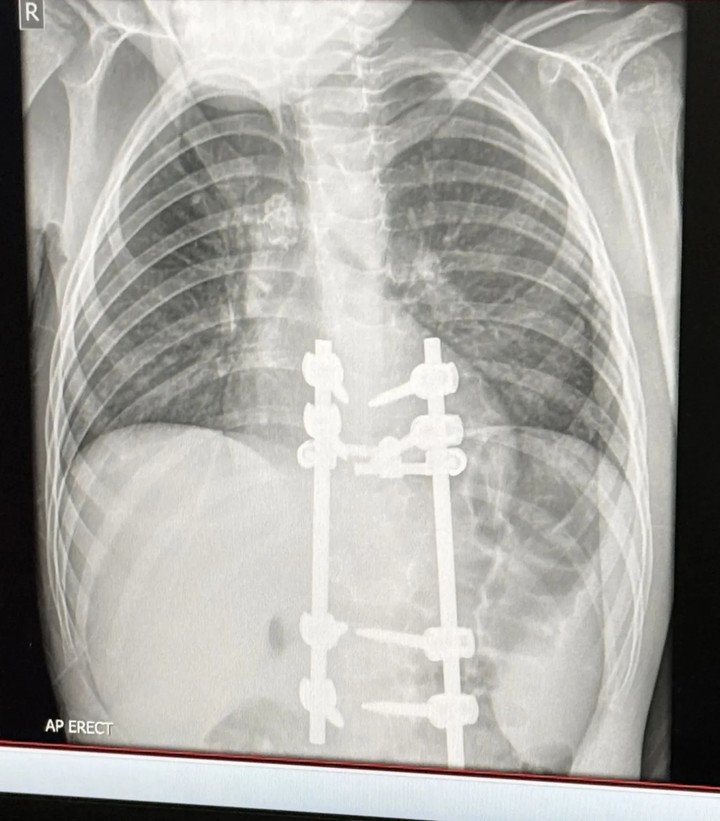

Sau khi đánh giá kỹ lưỡng, các bác sĩ chỉ định phẫu thuật đối với cậu bé Elliot, nhằm giải phóng chèn ép ống thần kinh và ổn định lại cấu trúc cột sống.

Ca phẫu thuật đầu tiên đã thành công, Elliot hiện có thể đi bộ, nhưng chưa được phép chạy nhảy. Cậu bé sẽ đối mặt với lần phẫu thuật thứ hai trong vòng sáu tháng tới, nếu dấu hiệu tổn thương lao trên cột sống không thu nhỏ. Theo chia sẻ từ người mẹ, dáng đi của Elliot đã trở lại bình thường, các cơn đau dữ dội ở vùng lưng cũng biến mất.

Kết quả X-quang của Elliot sau phẫu thuật. (Ảnh: Kennedy News)